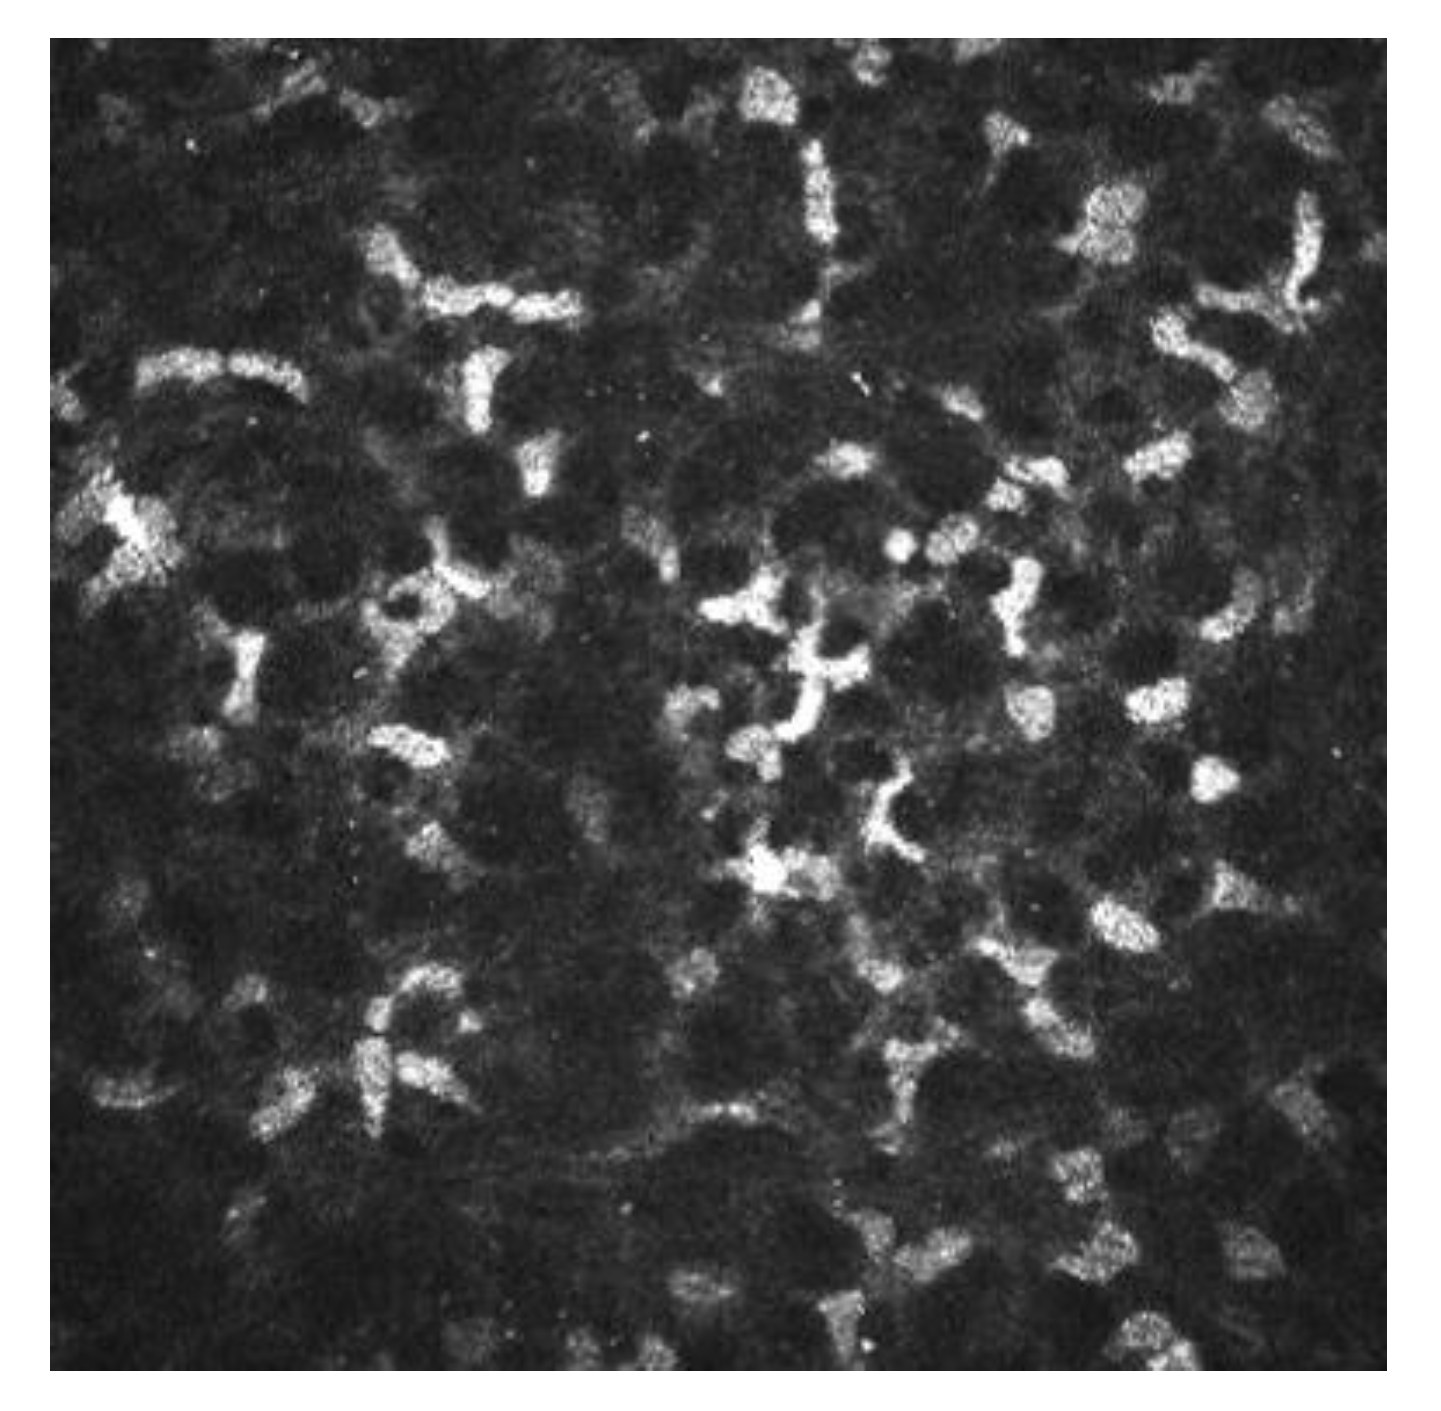

2.2. Sub-Basal Nerves

| Corneal Cells | Morphology | Reflectivity |

|---|---|---|

| Superficial epithelial cells | Polygonal, with different sizes | Hyperreflective nucleus surrounded by dark band |

| Winged epithelial cells | Polygonal, with different sizes | Hyperreflective without visible nucleus |

| Basal epithelial cells | Polygonal. Mosaic shape | Dark cell bodies with bright borders |

| Stromal cells (keratocytes) | Oval | Hyperreflective |

| Dendritic cells | Dendritic shape in active status. Oval shape in nonactive status | Hyperreflective |

| Nerve plexus | Lineal | Hyperreflective |

| Endothelial cells | Hexagonal shape | Bright cell bodies with dark borders |